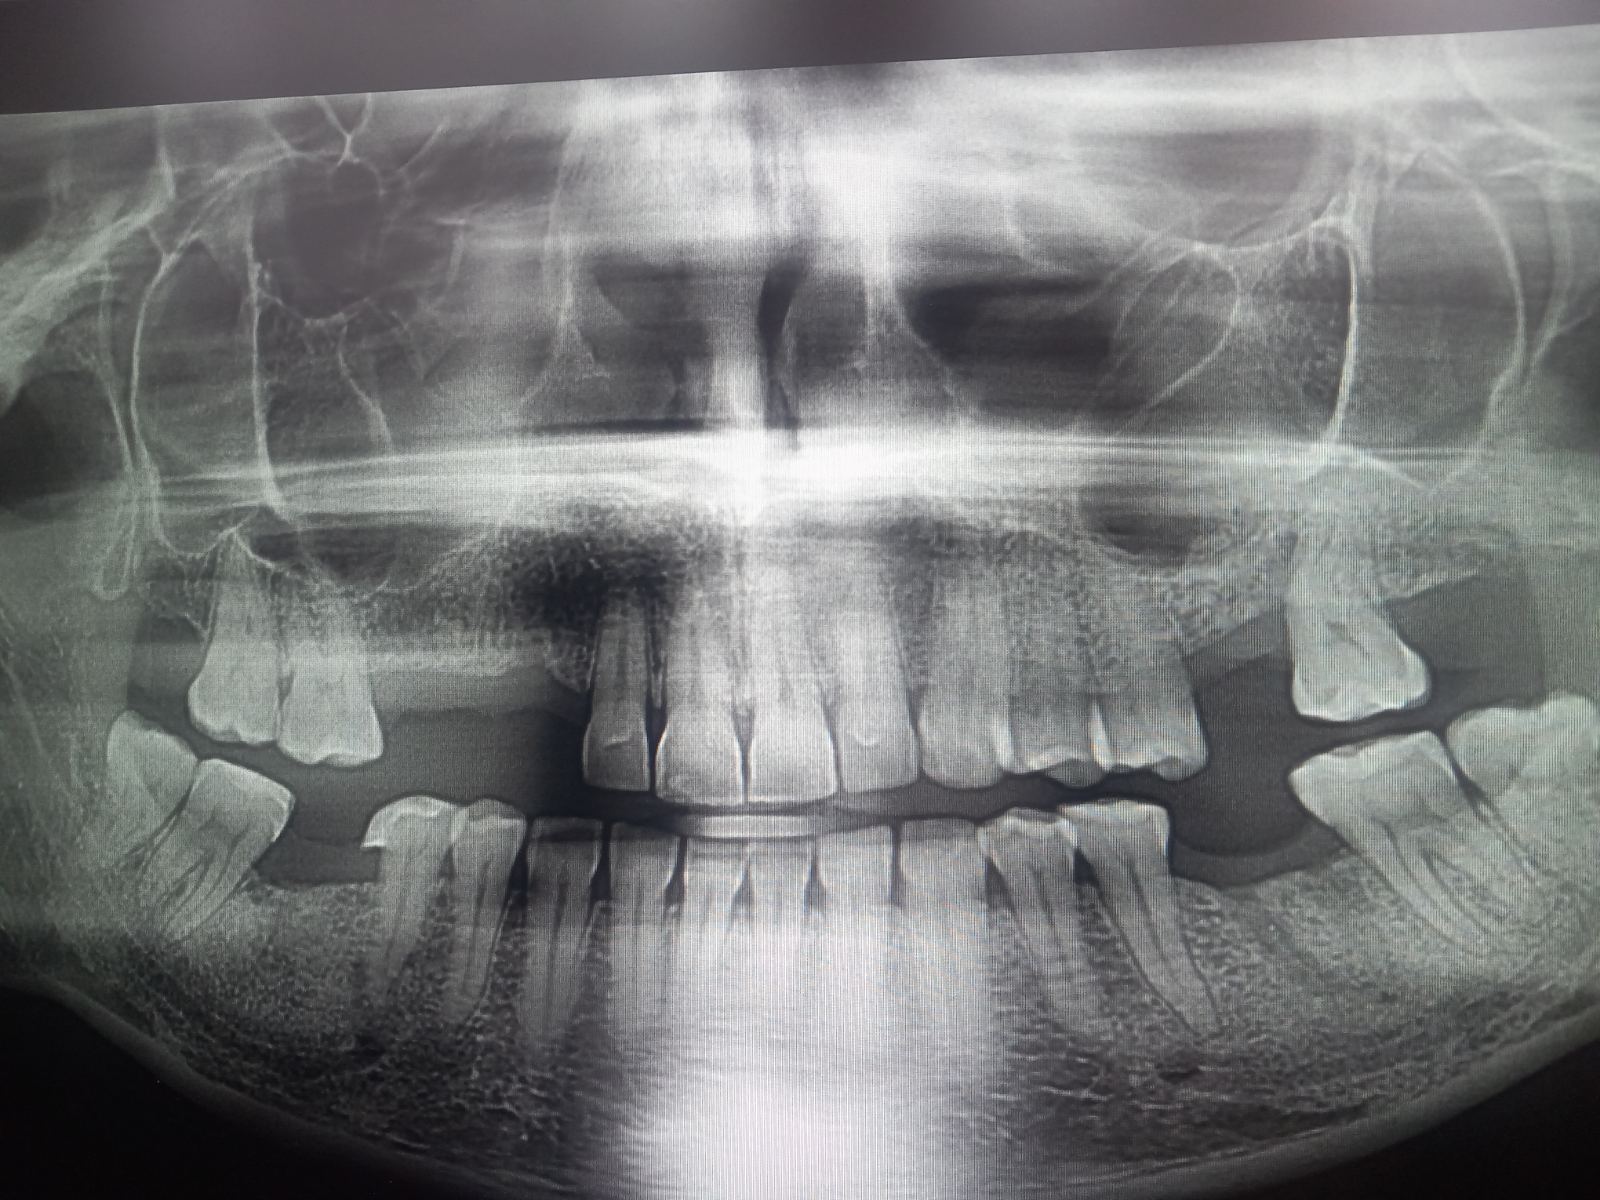

​Обръщаме се към вас с молба за помощ за една силна жена – Милена Стефанова Николова-Димова (43 г.). Милена се бори с тежко и агресивно заболяване на венците и челюстта (агресивна парадонтоза), което в последните месеци се влоши критично.

​Това, което започна като дентален проблем, се превърна в ежедневен кошмар от болка, възпаления и невъзможност за нормално хранене. Диагнозата е категорична: състоянието ѝ се влошава бързо и е нужна спешна хирургична намеса и поставяне на импланти, за да се спаси челюстта ѝ и да се спре разпространението на инфекцията.

Милена вече премина през болнично лечение (в УМБАЛ "Света Анна" и УМБАЛ "Медика"), но консервативните методи не са достатъчни. Всеки изминал ден без операция води до загуба на костна маса и риск от нови огнища на инфекция в организма.

Според плана за лечение от дентална клиника "ЕО Дент", общата стойност на първия етап (операция и импланти) е 6400 евро, а последващото протезиране възлиза на още 1710 евро. Общата сума от близо € 8000 е непосилна за Милена и нейното семейство.